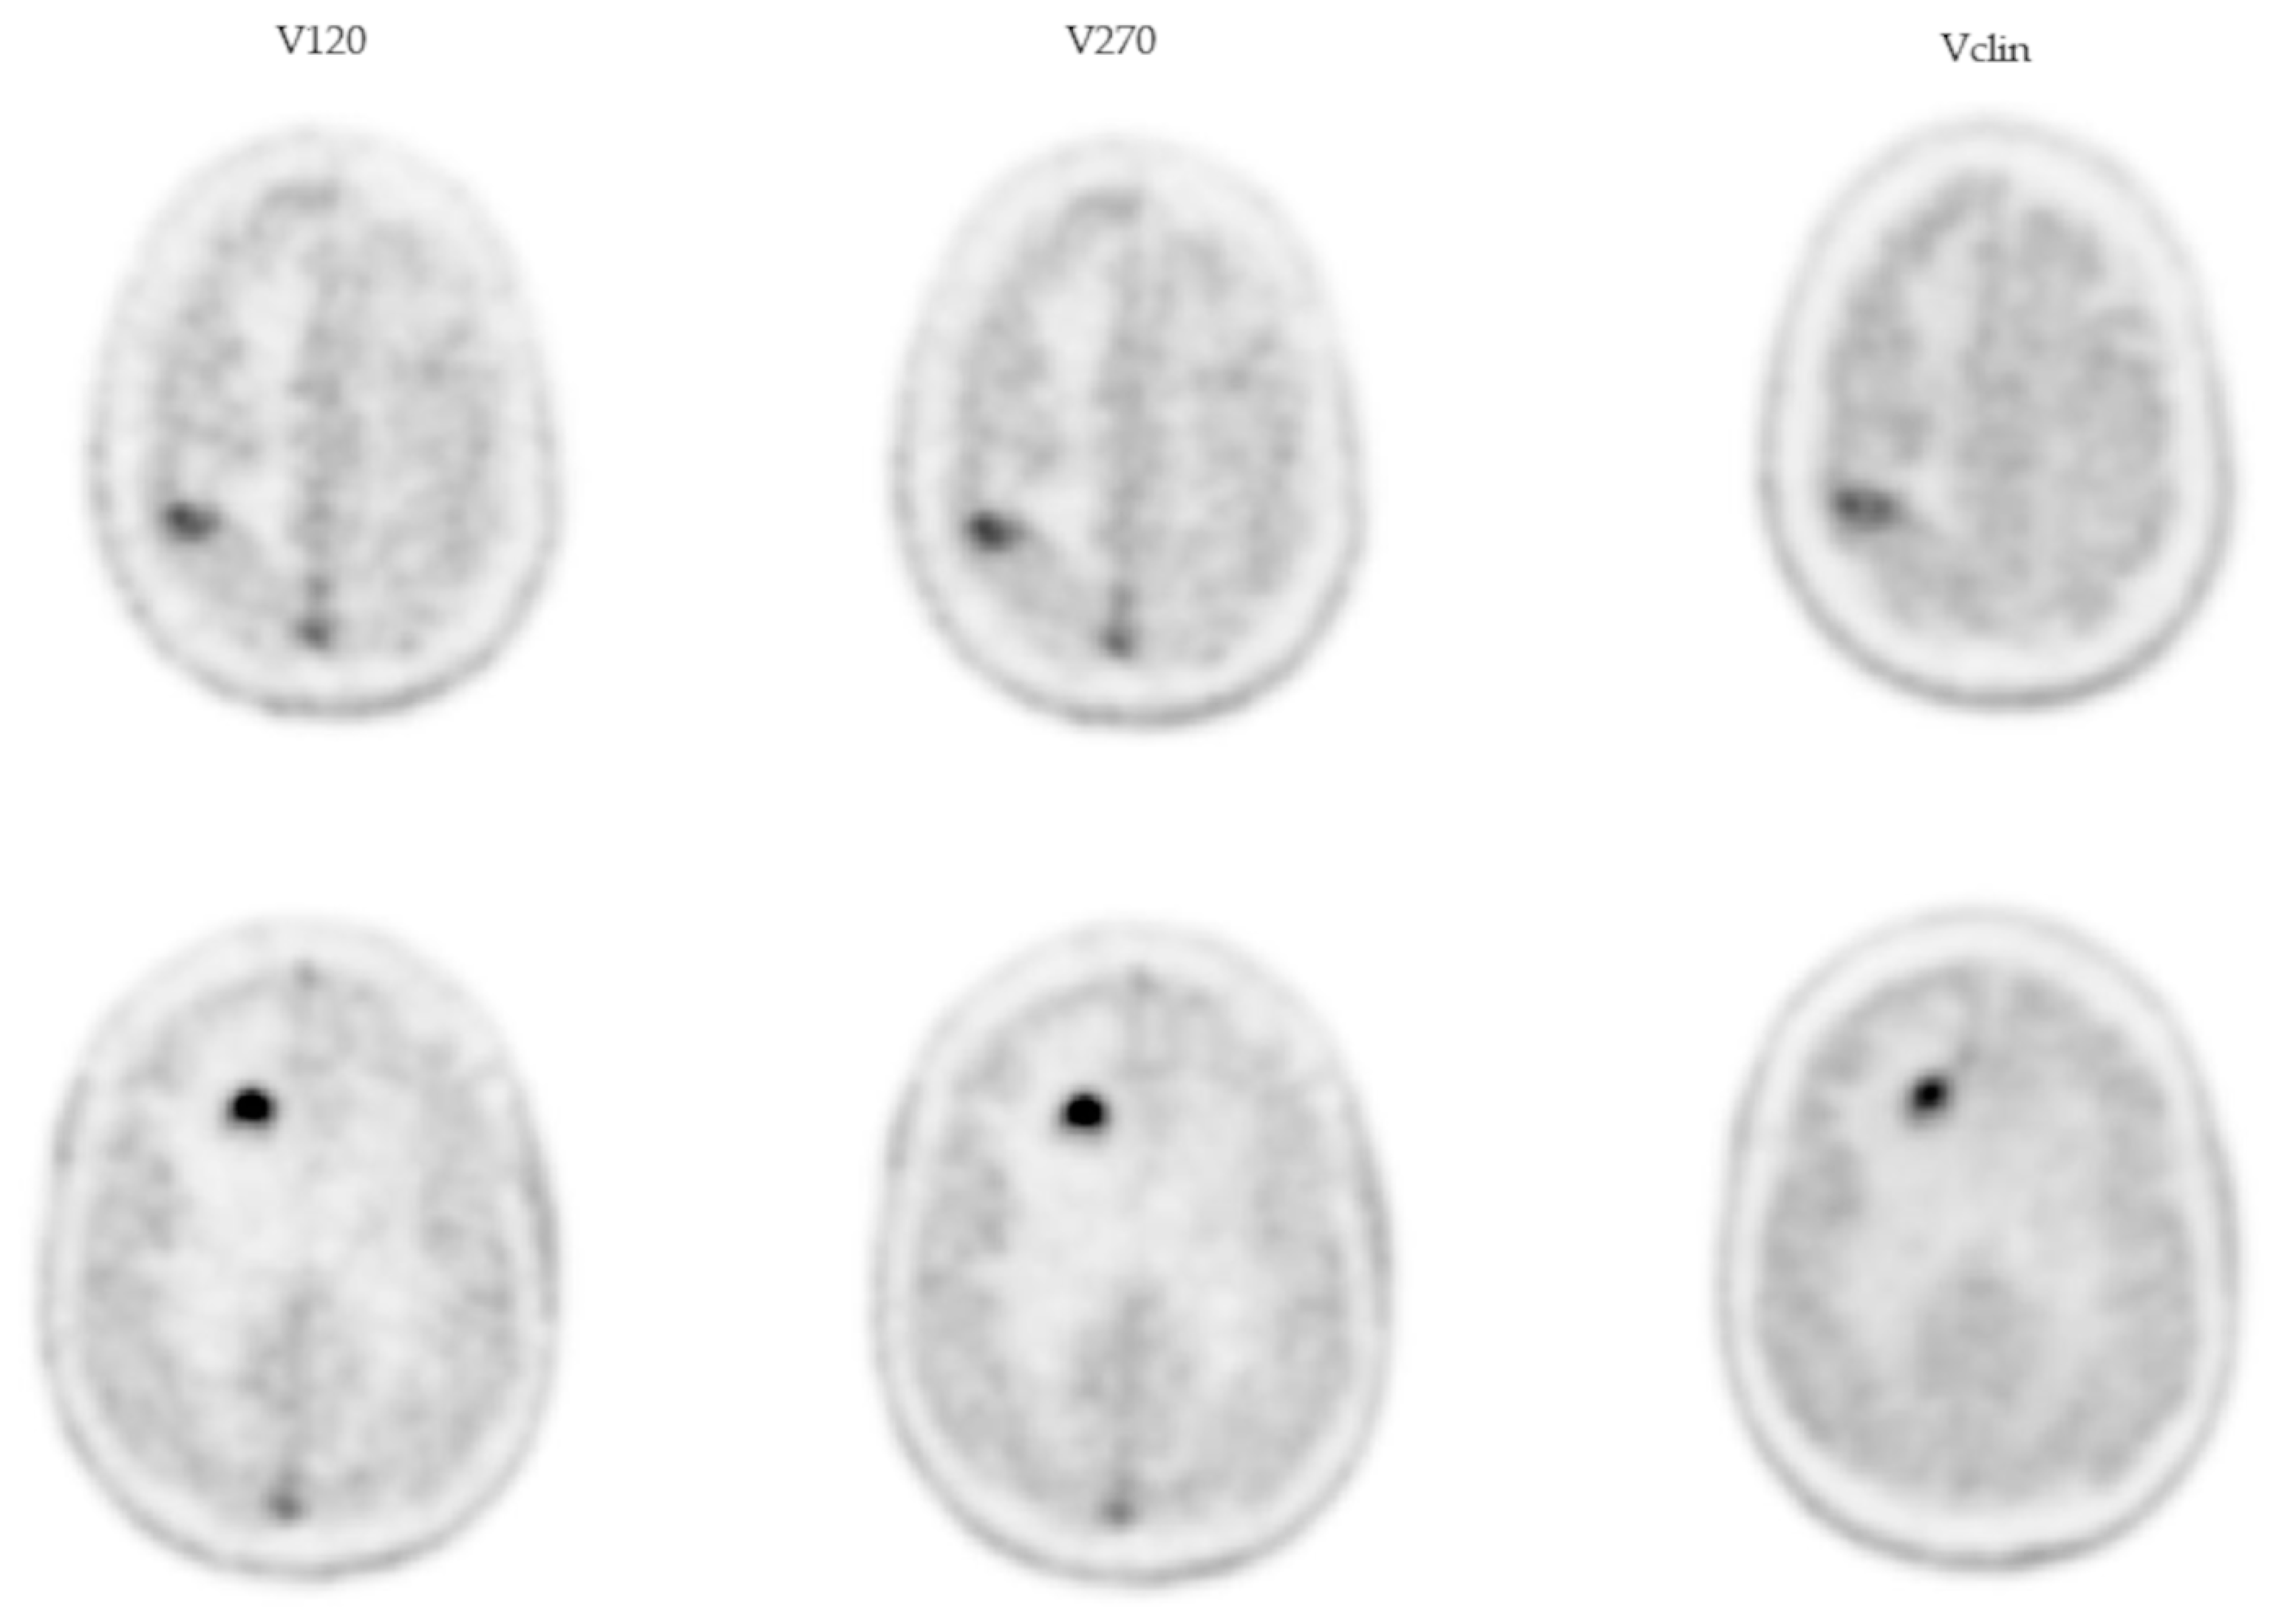

2.4. Experimental Volumes

2.5. The Clinical Volume

- (i)

- 2.19 (1.58; 2.80) and 4.87 (3.16; 11.17) for RN and MP, respectively, with regard to the V120 volume;

- (ii)

- 1.96 (1.32; 2.30) and 4.56 (2.96; 11.46) for RN and MP, respectively, with regard to the V270 volume;

- (iii)

- 1.95 (1.27; 2.28) and 2.70 (2.22; 5.75) for RN and MP, respectively, with regard to the Vclin volume.